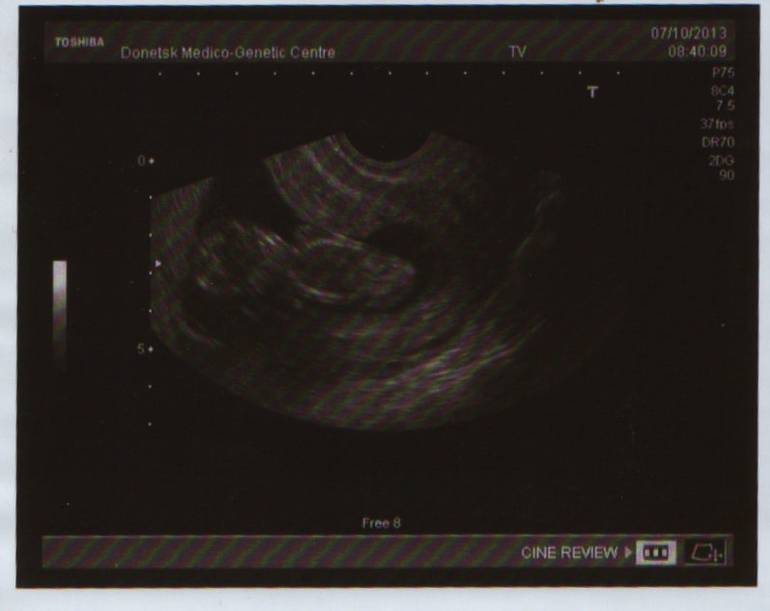

Вот наши размеры:

КТР - 55 мм

ЧСС -174 уд.

Толщина воротникового пр. - 1,5 мм

ОГ - 67 мм

ОЖ - 56 мм

Бедро - 5,5 мм

Интракраниальное пространство - 1,7 мм (что это не знаю??())

Венозный проток - 1,3 мм

Хорион - по передней стенке низко, 14 мм (интересно низко это плохо???)

Все определяется и ручки и ножки, и косточка носа)))

А еще по размерам мы уже обгоняем на два денька))) Вообще сегодня 11 недель и 6 дней, а по КТР - 12 недель и 1 день) Решила раз мы так на опережение, то изменила в настройках и тут))

Ну и фоточка нашей вредины - так лежит неудобно, что врач еле подлезла все измерить))